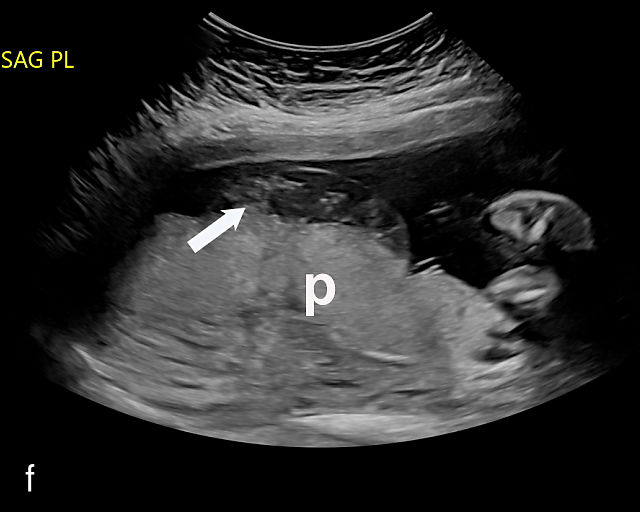

Placenta previa and low-lying placenta

In most pregnancies, the placenta implants in the upper part of the uterus. However, when the placenta implants in the lower uterine segment and overlies the cervix, it results in a condition called placenta previa, meaning the placenta is positioned ahead of the fetus in the birth canal.49 This positioning poses a serious risk during labor, as cervical dilation can cause premature placental separation, leading to severe, life-threatening bleeding for the pregnant patient.50,51 To prevent this hemorrhage, patients with placenta previa must be delivered by cesarean section before the onset of labor.51 Placenta previa complicates approximately 0.4% (1 in 250) of pregnancies at delivery.52 The strongest risk factor for placenta previa is a history of prior cesarean delivery.53,54,55 Maternal smoking, advanced maternal age and assisted reproductive technologies are also strong risk factors for placenta previa.56,57,58,59

Historically, placenta previa was most often identified in the early third trimester when patients presented with painless vaginal bleeding.49,60,61 However, with the widespread use of obstetric ultrasound in the second trimester, nearly all cases of placenta previa are now diagnosed incidentally in asymptomatic patients during routine scans. Notably, approximately 90% of placenta previa cases diagnosed in the second trimester will resolve by term due to placental ‘migration’ as the uterus grows.51,61,62,63,64,65 Thus, when placenta previa is diagnosed in the second half of pregnancy, the patient should have an examination close to delivery to determine whether the placenta previa is persistent or whether it has resolved. Generally, when a placenta previa is found at 20 weeks, a repeat ultrasound should be performed at about 32 weeks. In cases that persist at 32 weeks, a repeat scan should be performed around 36 weeks of gestation.66

In the past, placenta previa was classified as complete, partial, marginal or low-lying.50,61 However, with advancements in ultrasound technology allowing precise assessment of the relationship between the placenta and the internal cervical os, the classification has been simplified.67 Placenta previa now refers to cases in which the placenta overlies the internal os to any degree, while low-lying placenta describes cases in which the lower placental edge lies within 2 cm of the internal os (Figure 5).51,66,67

This distinction is critical in determining the mode of delivery.49,51 All patients with placenta previa persisting into late pregnancy require cesarean delivery to avoid complications such as severe bleeding.50,60,61 Studies suggest that patients with a lower placental edge located more than 1 cm from the internal os may safely attempt a vaginal delivery without a significant increase in bleeding risk.68,69,70,71

In patients with placenta previa and one or more prior cesarean deliveries, careful evaluation is necessary to rule out placenta accreta spectrum disorders, in which the placenta abnormally adheres to or implants deeply into the uterine wall.50,60

Most cases of placenta previa will be suspected prenatally by transabdominal ultrasound.49 However, this approach has several limitations and may be inaccurate.72,73,74 because the relationship between the placenta and the internal cervical os may be difficult to assess by transabdominal ultrasound.72,73,74 The bladder may be full, pushing the anterior and posterior walls of the lower uterine segment together, falsely creating the impression of a placenta previa (Figure 5e).61 There may be considerable shadowing, including by the fetal presenting part, which may limit the accuracy of transabdominal ultrasound (Figure 5d,f).75 Posterior placentas may be more difficult to assess.

Transvaginal ultrasound overcomes these limitations (Figure 5g–l).72,73,74,76 The probe is inserted into the vagina and therefore is closer to the region of interest.51,61 In addition, transvaginal transducers have higher frequencies and superior resolution compared to transabdominal transducers. Transvaginal ultrasound is safe and is not associated with increased bleeding.72,73,74,75,76 As such, transvaginal ultrasound should be the imaging modality of choice whenever there is suspicion of placenta previa.49,67,77